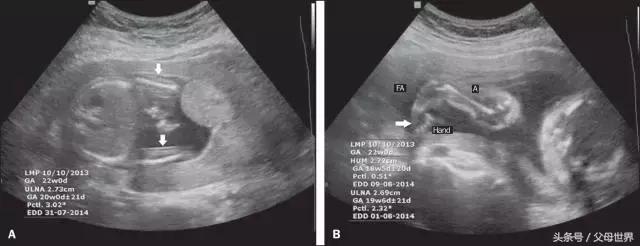

- 监测胎儿生长发育。主要通过测定双顶径(B P D)、头围(H C)、腹围(AC)及股骨长(FL),来判断孕周及胎儿的生长发育情况。此外,落后于正常生长发育的胎儿,有时还需测量身体各部分的比例,如头围与腹围的比例,能够更好地了解胎儿的生长情况。

BPD:双顶径,即胎儿头部从左至右最长的距离,足月时一般应达9.3厘米或以上。用于推算胎儿体重和发育状态。

FL:股骨长,即大腿骨长度,一般为BPD值减去2~3厘米(与孕周相关,可能会有差异)。用于推算体重。

HC:头围,即环头一周的长度,足月时可达34.5厘米。用于监测发育状态。

AC:腹围,即经过脐部肚子一周的长度,足月时可达36厘米。用于监测发育状态。